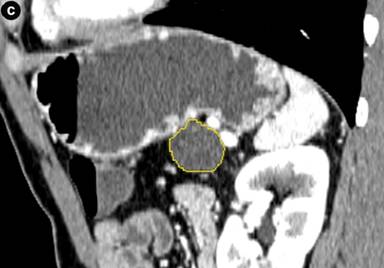

For measurement of the cyst diameter and volume, commercially available software (CT Oncology; Siemens Medical Solutions) was used on an image-processing workstation (Leonardo Workstation, syngo® 2008A MultiModality Workplace (VE26A) platform; Siemens Healthcare, Erlangen, Germany). Two independent investigators (H.C. and P.R.) with one and two years of experience using the software, respectively, performed the measurement on pancreatic parenchymal phase images. Pancreatic parenchymal phase was selected due to the superior conspicuity of the lesions in this phase. The application of this software in the volumetric measurement of abdominal masses has been described previously [13, 18]. The graphic user interface is divided into 4 screens: axial, coronal, sagittal and 3D views. Once the investigator identifies the pancreatic mass by drawing an approximate line across it, the software selects the entire lesion. This is achieved by three-dimensional reasoning by the software to remove neighboring normal pancreatic tissue, hence, generating a volume of interest around the drawn line and extends the segmentation on the basis of histogram analysis within the generated volume on interest (Figure 2). The selections can be edited by the investigator in x, y, and z planes, if necessary.

Figure 2. Coronal (a.), axial (b.), sagittal (c.) and three dimensional (d.) CT images of a histopathologically proven pancreatic tail mucinous cystic neoplasm in a 39-year-old man. Despite a dilated pancreatic duct no connection was visualized on endoscopic ultrasound with the cyst. Borders of cyst are marked with yellow line by the software. CT volumetry (22.3 mL) and an elongation value (0.67) for the cyst were automatically generated by the software once the measurement was finalized by the observer. Pancreatic head cyst was not segmented because of apparent connection with the pancreatic duct that was dilated. Also, note that the patient was a male with mucinous cystic neoplasm, an extremely rare occurrence. |